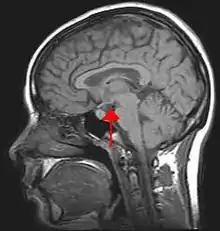

Hypothalamus et motivation

L'hypothalamus peut être également associé à la motivation de comportement assouvissant certains besoins physiologiques tels que la soif et la faim. Cet « expert » du système végétatif, est le « commandeur » de ces comportements. En effet, « l'hypothalamus peut être considéré comme un véritable ordinateur de la vie végétative qui programme les composantes physiologiques de la faim, de la soif, de la sexualité, de l'ovulation, les rythmes de base du sommeil, etc. »[30]. De plus, ce deuxième facteur explicatif de la motivation est directement relié au système limbique, qui est au centre des émotions humaines, et ainsi, permet de déclencher, ou inhiber, des comportements agressifs.

Par exemple, la stimulation de l'hypothalamus médian ventral entraîne le déclenchement de la lutte, alors qu'au niveau dorsal, il déclenche la fuite. L'hypothalamus latéral, stimulé cholinergiquement, déclenche soit la soif, soit l'agressivité.